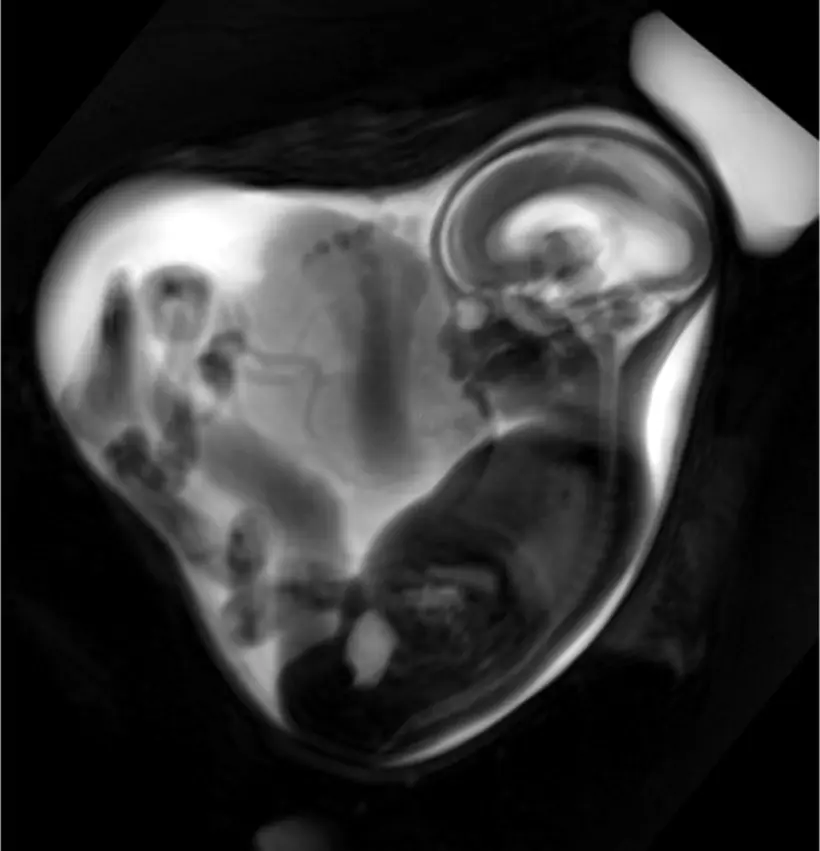

Die Magnetresonanztomographie (MRT) ist ein bildgebendes Verfahren, das mithilfe von starken Magnetfeldern und Radiowellen detaillierte Bilder von Organen und Geweben erzeugt. Eine MRT des Kopfes wird häufig zur Diagnose verschiedener Erkrankungen des Gehirns, der Hirnhäute, der Augen und der Ohren eingesetzt. In der Schwangerschaft ist die MRT ein wichtiges Instrument, um den Zustand des Fötus zu beurteilen und mögliche Komplikationen frühzeitig zu erkennen.

MRT Kopf Schwangerschaft: Was wird untersucht?

Eine MRT des Kopfes während der Schwangerschaft kann verschiedene Aspekte untersuchen, darunter:

- Entwicklung des Gehirns: Die MRT kann die Entwicklung des Gehirns des Fötus beurteilen und eventuelle Auffälligkeiten feststellen.

- Position des Fötus: Die MRT kann die Position des Fötus im Mutterleib darstellen und feststellen, ob der Fötus in einer ungünstigen Position liegt.

- Mutterkuchen: Die MRT kann den Zustand des Mutterkuchens beurteilen und eventuelle Auffälligkeiten feststellen.

- Flüssigkeit im Gehirn: Die MRT kann die Menge an Flüssigkeit im Gehirn des Fötus beurteilen und feststellen, ob es Anzeichen für eine Hydrozephalus gibt.

- Geburtsdefekte: Die MRT kann bei der Diagnose von Geburtsdefekten des Gehirns und des Schädels helfen.